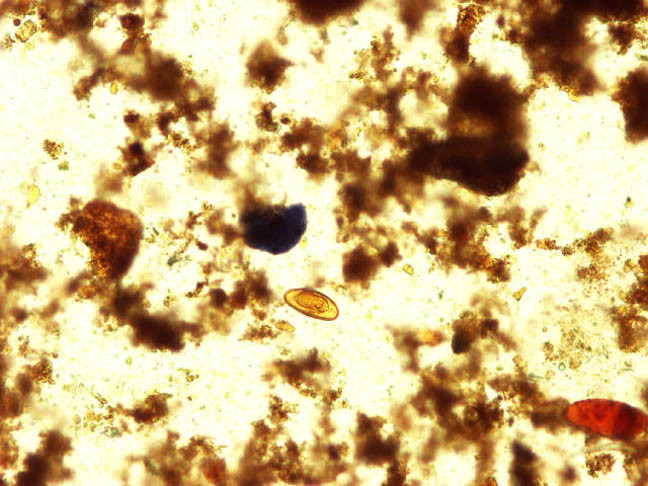

Enterobius Vermicularis

- 10x

Enterobius 10x

Notice the flat edge